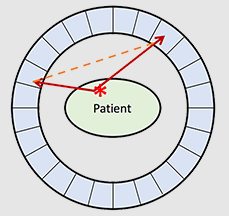

What is a random coincidence?

This is when two annihilation events happen at the same time – this will hit 4 detectors but only 2 will activate and will create a false line of response

However, this line of response cannot be ignored as it fulfills the objective of having two 511 keV photons

How does a random coincidence happen?

Happens when there is too much radioactivity

What happens to our images if there are random coincidences occurring?

Will create a bad image as there are too many random events – PET camera cannot differentiate between the many different annihilation reactions happening